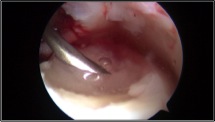

Nei casi più importanti, dove le lesioni cartilaginee sono più gravi e localizzate in zone di carico dell’astragalo, una valida soluzione è rappresentata dall’utilizzo di tecniche chirurgiche avanzate di riparazione cartilaginea che utilizzano supporti tridimensionali in grado di veicolare le cellule cartilaginee e colmare così il difetto che si è creato. Queste tecniche possono essere eseguite anche in artroscopia con maggior rispetto dell’articolazione e tempi di recupero post-operatorio di circa 3-4 mesi.

Naturalmente il trattamento chirurgico della cartilagine deve essere assolutamente associato ad una stabilizzazione dell’articolazione, nei casi di instabilità articolare, altrimenti ogni gesto chirurgico sarà destinato al fallimento in tempi più o meno brevi.